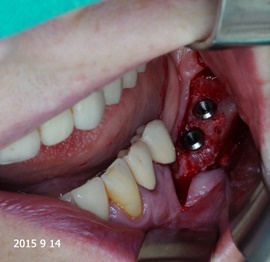

Pacjentka lat 72, od kilkudziesięciu lat chorująca na cukrzyce I typu, obecnie od 10 lat na pompie insulinowej. Profesor medycyny, siostrzenica pacjentki prowadzi swoją ciocię diabetologicznie, pacjentka świadoma zagrożeń przy zabiegach regeneracji kości i implantacji w takim ogólnym stanie zdrowia. Po rekonstrukcji tkanek miękkich i kości osadzono dwa implanty o średnicy 5,0 mm. Na zdjęciu śródzabiegowym widać zadowalające wyniki rekonstrukcji tkanki kostnej. Po upływie kilku miesięcy wykonano nadbudowę protetyczną.